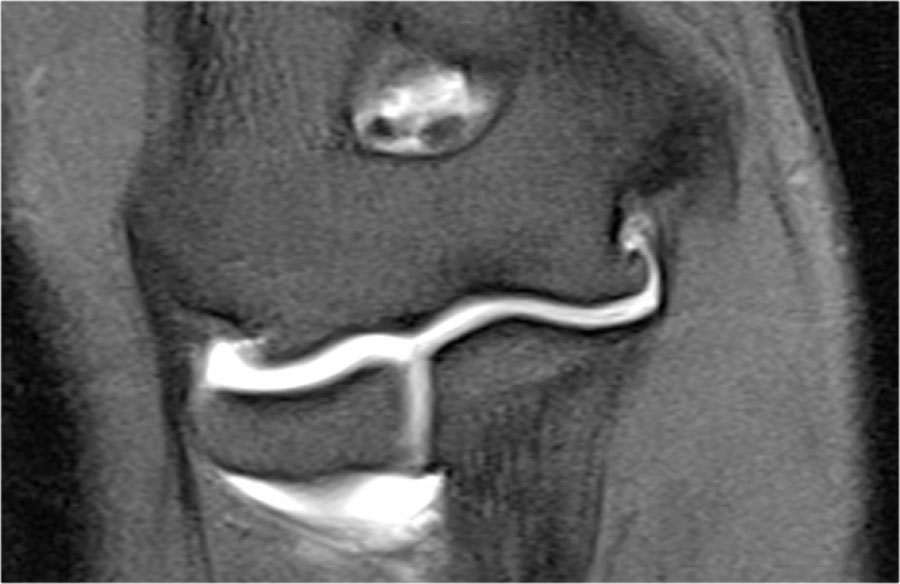

Plica

Cấu trúc này ở phía bên ngoài của khớp đôi khi được nhìn thấy và là một nếp gấp hoạt dịch (plica).

Nó có thể nổi bật và trông gần giống như một sụn chêm.

Đây là một cấu trúc bình thường, nhưng đôi khi nó bị dày lên hoặc không đều và có thể là nguyên nhân gây ra các triệu chứng.